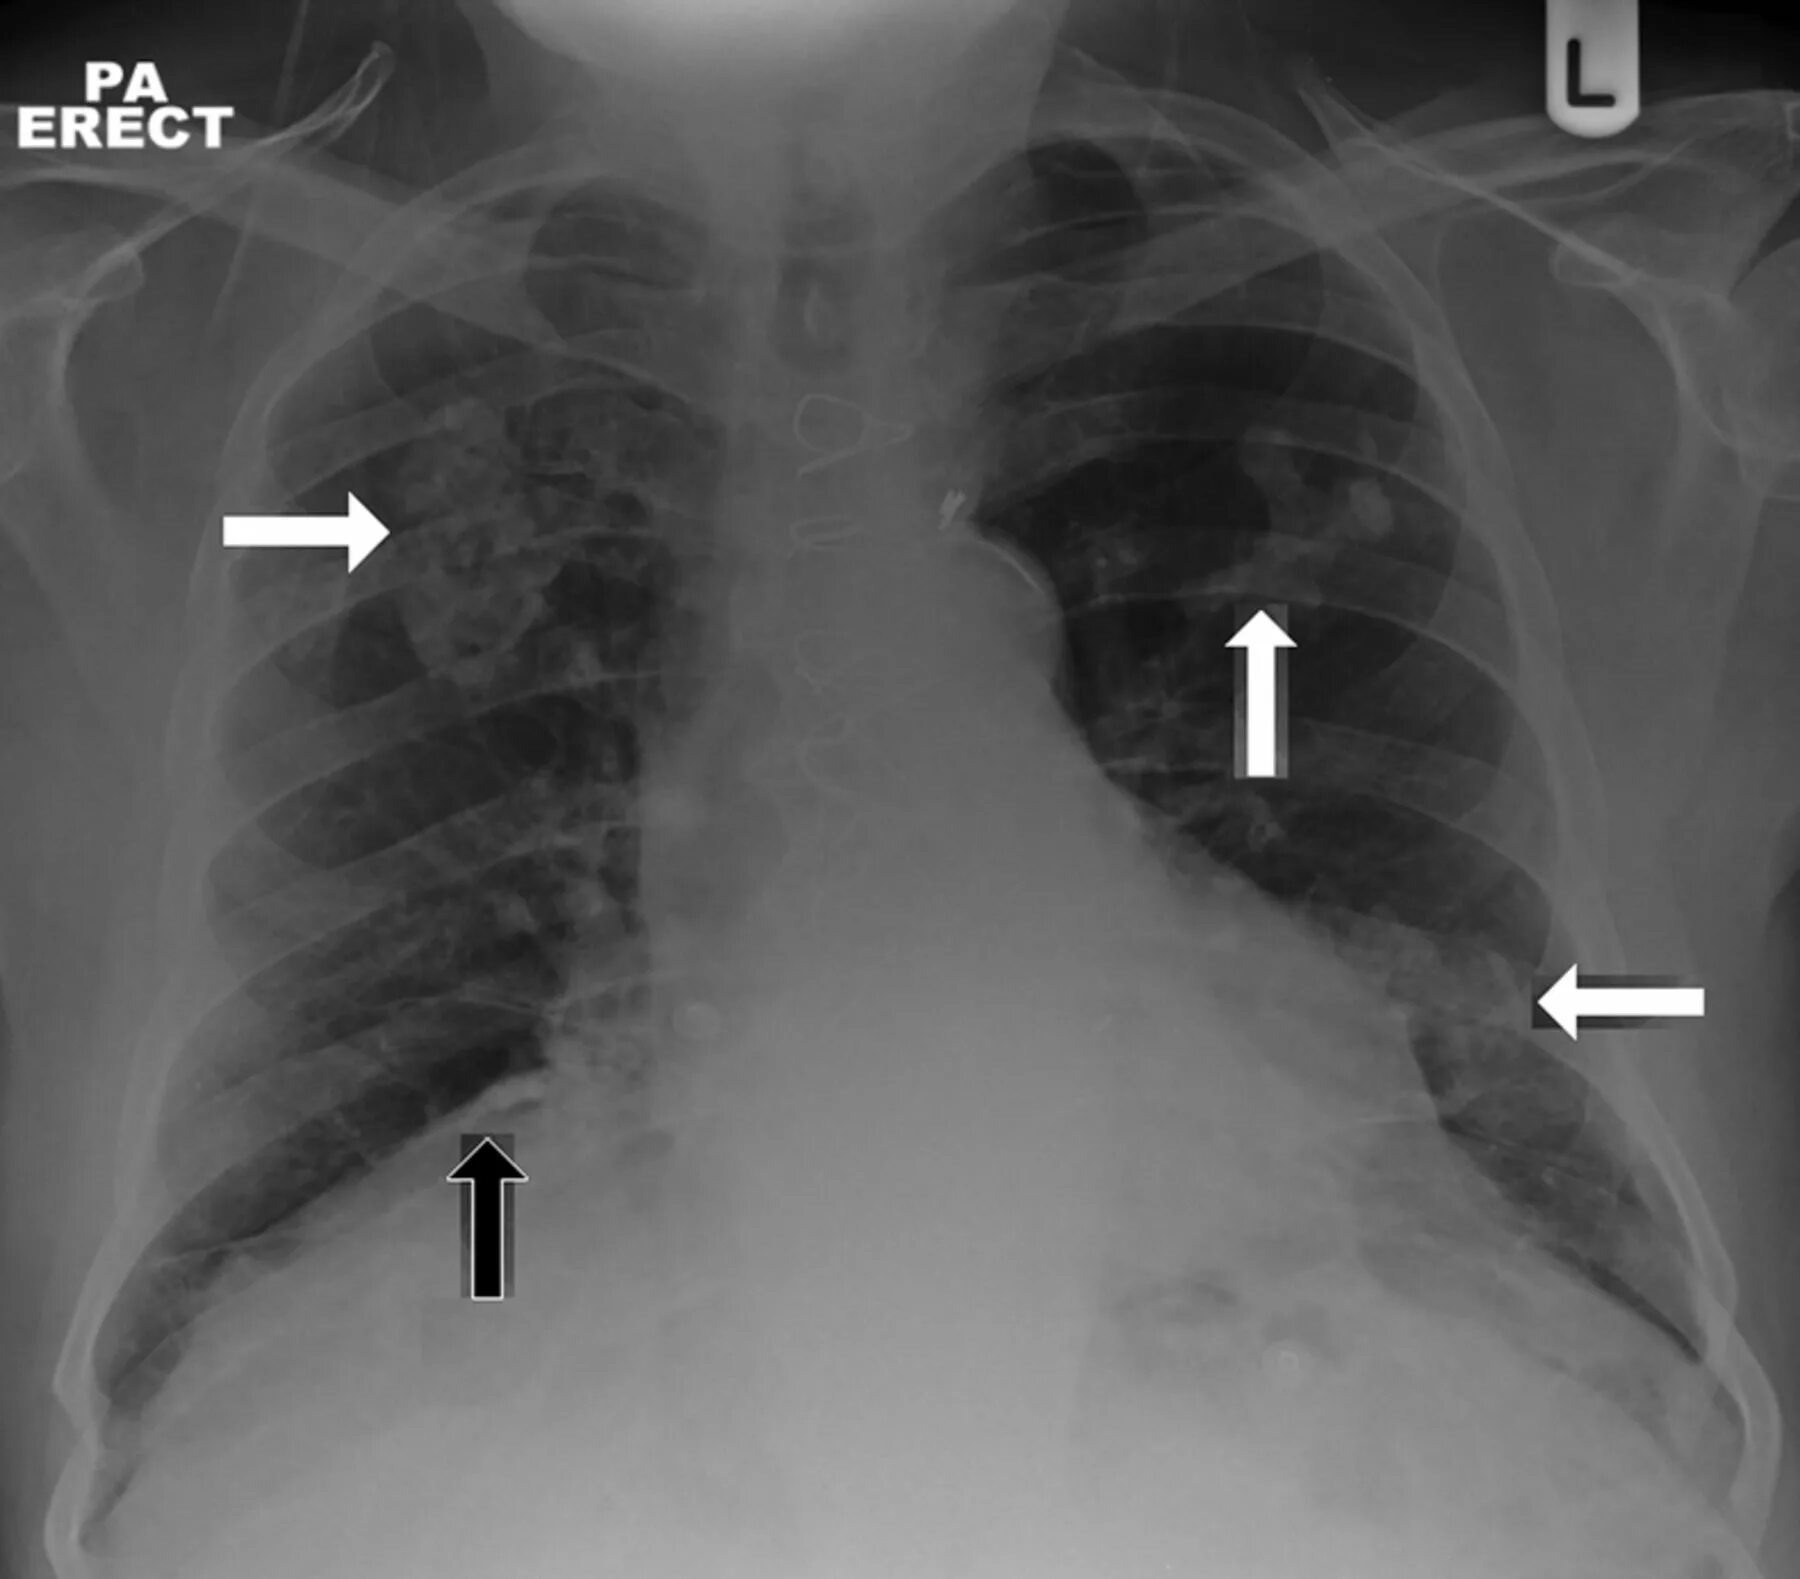

Метастазы плевры